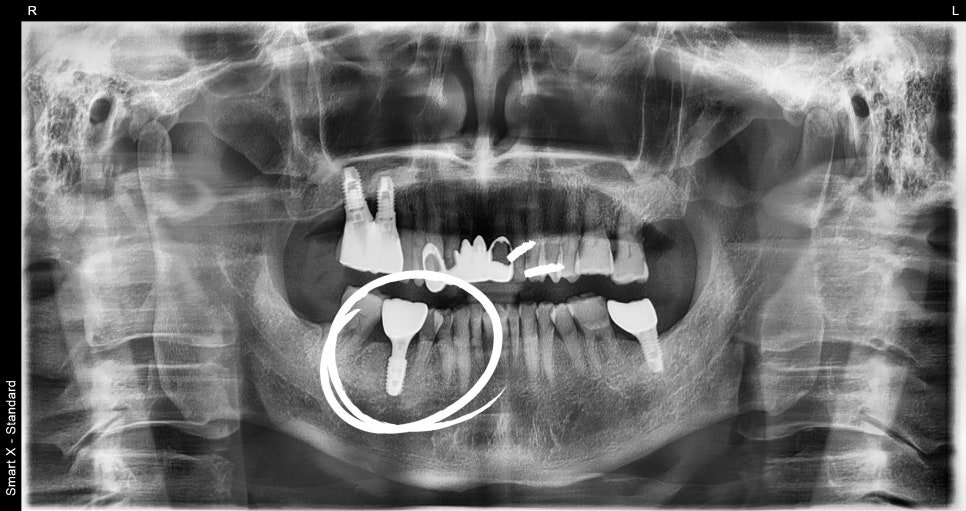

Implant Recovery Period

An implant is not a treatment that is completed

immediately after placement.

It takes a certain period of time for the implant and bone to integrate. Usually, this takes about 2 to 3 months,

and at Seoul Ob Dental Clinic,

progress is continuously monitored during this period.

Implant price can be seen as the cost that includes the entire treatment process.